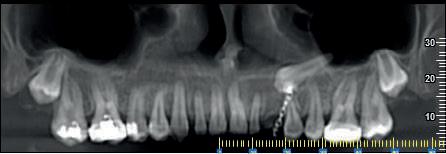

La diagnostica per immagini si avvale di tecniche 2D (Ortopanoramica dentale e full endorale) e 3D (3D Cone Beam Computed Tomography - CBCT).

La 3D CBCT consente la perfetta localizzazione, posizione, versione del canino incluso, la valutazione dei rapporti con gli elementi dentali limitrofi ed eventuali contatti di allarme con le strutture anatomiche critiche (seno mascellare, CNP, fossa nasale, forcazione del premolare superiore).

Le notizie fornite al clinico sono necessarie nella pianificazione della terapia di disinclusione, che può essere ortodontica e/o chirurgica.

Nel presente articolo presentiamo 3 casi di inclusione del canino superiore.

Fig 2 : stesso Paziente. Ricostruzione panorex.

Il 13 è incluso per ostacolo di eruzione relativo alla presenza di minuti denticoli (odontoma composto).

In emiarcata sinistra, come reperto collaterale, si osserva persistenza di 63 ed agenesia di 23.

Fig 3 - Fig 4 : Paz F. aa 12

Il 13 ed il 23 sono inclusi in posizione alta, mesioangolati, con associate ampie cisti follicolari.

Il 13 è visibile dalla sezione radiale 21 alla 26.

La cuspide di 13 è craniale al 12.

Le cisti follicolari assottigliano, e a destra in parte discontinuano, i tavolati corticali vestibolare e palatale.

Si rileva inoltre rizalisi di 12. 21. 22 relative alla estensione delle lesioni cistiche.

Fig 5 - Fig 6 : Paz F aa 16 Ricostruzione panorex e sezioni radiali dell’emiarcata sinistra.

- Il 23 è in trazione ortodontica per inclusione alta in posizione mesio-trasversa, contiguo al pavimento della fossa nasale sinistra ed al pavimento del seno mascellare sinistro.

L’apice radicolare di 23 si impegna nel pavimento del seno mascellare sinistro; la cuspide erompe in versione vestibolare, craniale all’apice radicolare di 24.